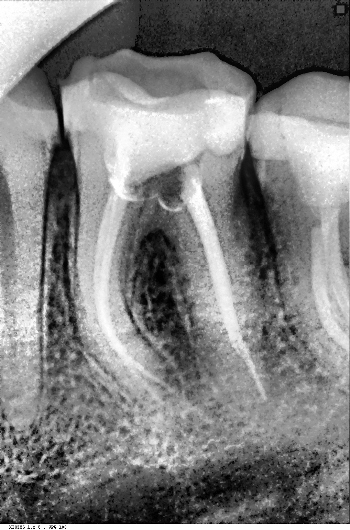

Внешних изменений нет. Открывание рта свободное. В полости рта: 3.6 глубокая кариозная полость на медиально-жевательной поверности, выполнена остатками пищи, старой пломбы и большим количеством размягченного пигментированного дентина. Полость зуба не вскрыта, зондирование стенок и особенно дна кариозной полости болезненно. При воздействии раздражителей (температурных и химических) возникает длительная ноющая, постепенно затихающая боль.

Перкуссия безболезненна и незначительно чувствительная. Ранее получала лечение по поводу глубокого кариеса (восстановлен объёмной пломбой).

Ортопантомография - деструктивные изменения костной ткани у верхушек корней.

Диагноз: Хронический пульпит.

Под проводниковой анестезией Sol.Ultracaini Sol.Ultracaini 1:200 000- 1.7 мл. проведена механическая обработка и формирование кариозной полости, раскрыта полость зуба, создан доступ к корневым каналам. Проведена глубокая ампутация коронковой и экстирпация корневой пульпы. Эндодонтическое лечение путём инструментальной обработки под визиографическим контролем.

Каналы пройдены до верхушки, определена рабочая длина канала. Дистально-щёчный канал - 20мм, медиально-щёчный канал - 20мм, язычный канал - 21 мм, произведена инструментальная обработка (прохождение и расширение) каналов ручным инструментом и с помощью эндодонтического наконечника. Медикаментозная обработка каналов 2% р-ром хлоргексидина. Высушивание каналов бумажным штифтом, пломбирование гуттаперчей методом латеральной конденсации, пастой «Foredent» под контролем визиографии - каналы зуба запломбированы однородно на протяжении, гомогенно. Изменений в периапикальных тканях нет.